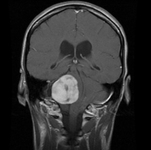

Neuroma acústico: ressonância nuclear magnética (RNM) coronal pós-contraste

Do acervo do Ryojo Akagami; usado com permissão